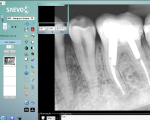

Saevo Digital Sensor

Sensor